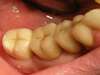

Cas n°1 :